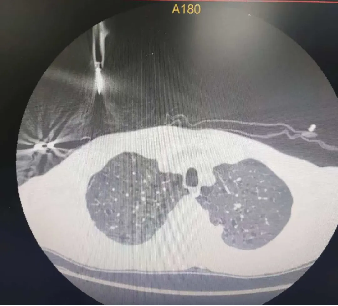

其次,精准医疗在呼吸科疾病诊断中也发挥着重要作用。借助先进的影像学技术和人工智能算法,医生能够更精准地识别肺部疾病的类型和分期。例如,在肺癌的诊断中,通过CT或彩超引导下的穿刺活检,结合病理学和分子分型技术,医生可以明确肿瘤的基因变异情况,为制定精准的治疗方案提供依据。

此外,呼吸介入治疗作为精准医疗的重要组成部分,在呼吸科的应用日益广泛。例如,对于晚期肺癌患者,呼吸科医生可通过气管镜、经皮穿刺介入治疗等方法,进行气道内病灶祛除、支架置入、球囊扩张、局部消融及冷冻等治疗,以缓解呼吸道症状,提高患者的生活质量。这些介入治疗技术不仅创伤小、恢复快,而且能够精准定位病灶,实现个性化治疗。